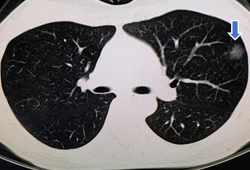

▲右肺下叶背段肺门旁不规则软组织,周围见毛刺